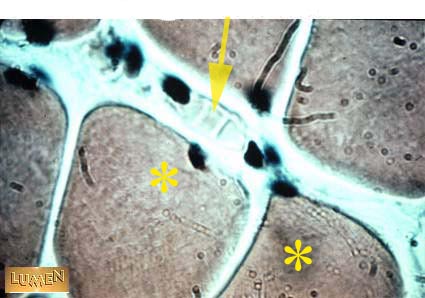

Q1 What kind of cell is identified by the asterisk?

Q2 The arrow points to what cells?

Answer 1

Skeletal muscle cell

Answer 2

RBC